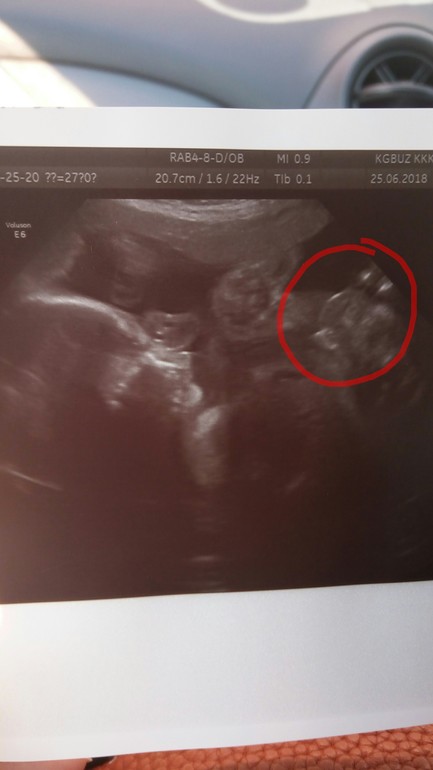

Таки мальчик )))

Пол малышаИз за предлежание отправили меня в 27 недель на Узи, в этот раз фото писюнчика получилось ))))